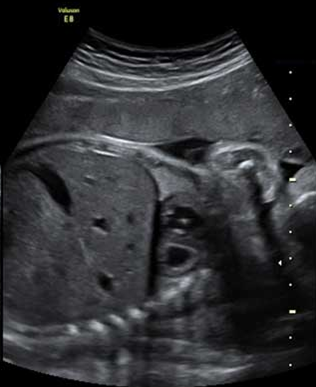

产科_胎儿_早孕单胎三维成像

产科_胎儿_早孕双胎三维成像